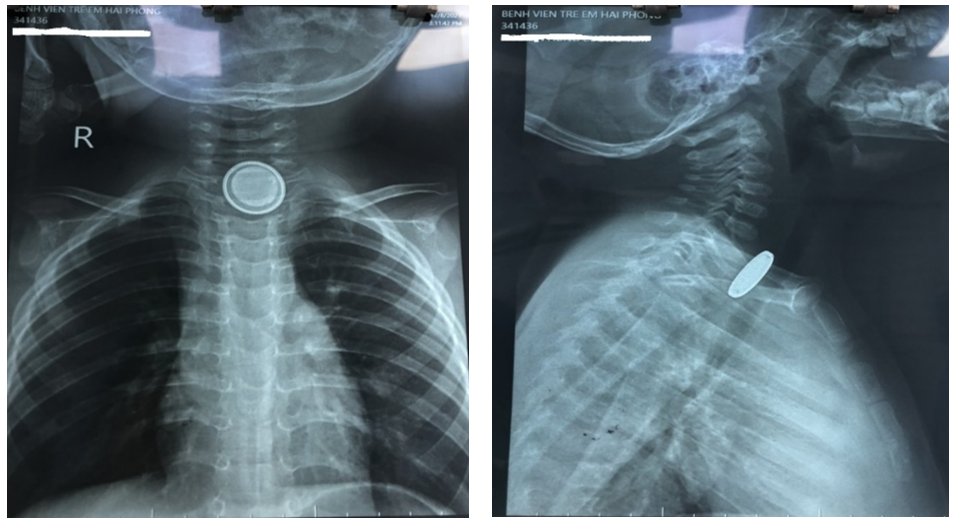

khoa Tai Mũi Họng trẻ được các bác sỹ thăm khám, chỉ định chụp phim X quang cổ và ổ bụng, kết quả có hình ảnh dị vật cản quang là 2 hình

tròn đồng tâm ngang mức cổ 6,7.

Hình ảnh dị vật pin cúc trên phim chụp X quang cổ